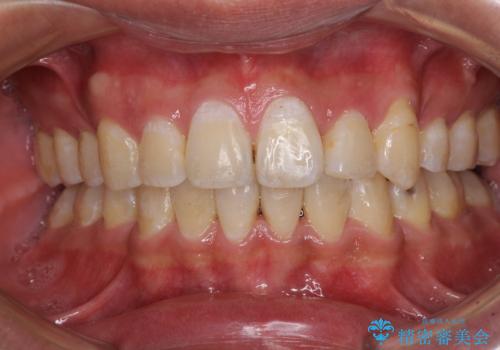

奥歯の咬み合わせを改善したいため、治療期間が長くなりましたが、患者様には辛抱強くお付き合いいただきました。

上下の正中を合わせることもでき、患者様には大変満足していただきました。